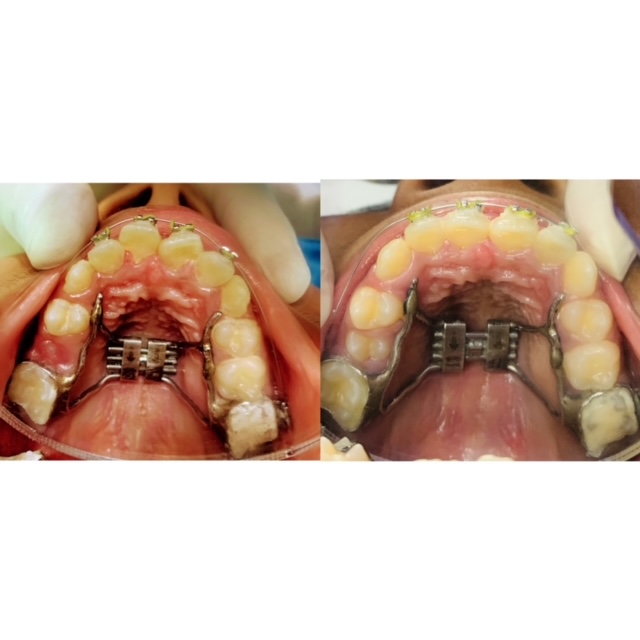

RME Rapid Maxillary Expansion (sometimes called rapid palatal expansion) is a technique used to widen (expand) your upper jaw (palate) when it is narrow. The expander appliance is a fixed brace made from a mould of your teeth to fit your mouth only. It is fixed to the upper teeth. You cannot remove it without your dentist’s help. The RME moves these two halves apart and holds them there while new bone fills in the “gap” under the gum. The metal framework contains an expansion screw in the middle to widen the upper jaw. It is attached to metal bands cemented on the back teeth or to a plastic splint which is cemented firmly to the back teeth. The expansion screw in the metal framework needs to be turned, usually twice a day or as instructed by your dentist for which a special key is given to you for this purpose.

The RME appliance has to be worn for a period of 3-9 months. In the initial course of 2-3 weeks, the upper jaw bone widens (up to 6mm). In the remaining months, it is left alone to allow new bone to fill in the gap under the gum between the two halves of the upper jaw. Treatment is mostly completed with a fixed brace to straighten your teeth. The Expander, due to its shape memory, progressively expands like a compressed spring in a very controlled and comfortable way.